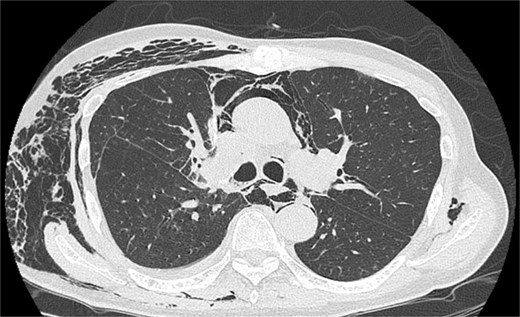

A man in his 70s presented for evaluation of a lung nodule on follow-up computed tomography (CT) 1 year postsurgery for early gastric adenocarcinoma. He had a history of heavy smoking (1.5 packs per day for 50 years) and had quit 1 year prior. CT revealed a 1.5 cm irregularly marginated solid nodule in the apical segment of the right upper lobe (Fig. 1a). Positron emission tomography (PET) revealed a maximum standard uptake value of 4.6 on the nodule (Fig. 1b). PET and brain magnetic resonance imaging revealed no metastases. All tested serum tumour marker values were within normal ranges. CT revealed emphysema of the lung. Pulmonary function tests indicated a forced expiratory volume in 1 s (FEV1.0) of 2130 ml and an FEV1.0/forced vital capacity ratio (FEV1.0%) of 65.3%. Bronchoscopic biopsy was not performed owing to difficulty in obtaining an informative specimen, and the lesion was suspected to be primary lung cancer. Although the size and location of the nodule met the criteria for intentional limited resection to treat lung cancer [3], lobectomy was considered more appropriate than apical segmentectomy for a sufficient margin and tolerable pulmonary function.

On POD 6, SE developed and spread to the chest, neck, and face. CT demonstrated remarkable mediastinal and SE with minimal lung collapse (Fig. 2; Video 2). Therefore, a chest tube was inserted, but minimal AL occurred from the chest tube, and the emphysema worsened. On POD 11, we performed thoracoscopic exploration and therapeutic intervention. Dense adhesion was confirmed between the staples on the interlobular plane and the dissected upper mediastinum. These were released, revealing the previous pleural tear. No other causative factors were observed. CT and operative findings suggested late-onset AL into the dissected mediastinum through dense adhesions. A leak test under positive pressure of up to 20 cmH2O revealed no AL from the pleural tear. The tear was sealed using a PGA sheet and fibrin glue, and 130 ml of autologous blood was injected into the pleural space to seal the dissected mediastinum and prevent air inflow (Video 3).

Image of postoperative mediastinal and SE with little lung collapse.